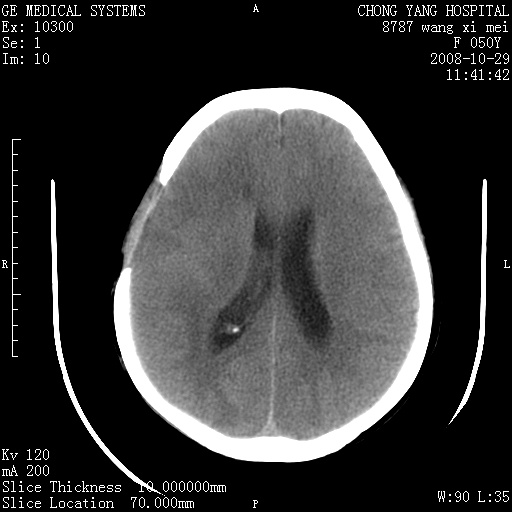

右侧颞顶部可见低密度实变影,内见不规则钙化灶,边界不清,占位效应明显,侧脑室后角受压移位,符合胶质瘤术后复发改变。

右颞骨局限性缺如,局部脑组织无外隆。右颞叶可见片状脑脊液样低密度影,边缘较清,右侧侧脑室三角区可见一块状等密度影,且伴有强化,余未见明显异常改变。

考虑:右大脑术后改变伴肿瘤复发。

手术后局部片状低密度改变(软化灶),其后方颞叶似等密度病灶,界限不清,内见钙化,有轻度占位效应,但增强后强化之血管走行如常。应不考虑:复发!

考虑右侧颞顶叶胶质瘤术后复发。

应考虑肿瘤复发,右颞顶叶已出现轻度强化肿块.必要时可与原片比较以下.

右侧颞顶部混杂密度影,内有钙化,有占位效应。应该是复发灶。结合术后片更好。